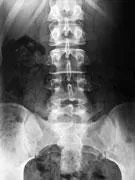

Tous les os peuvent être touchés augmentant ainsi les risques de chutes et de fractures, mais les plus atteints sont le col du fémur, les vertèbres, les os de l'avant-bras, le col de l'humérus.

L'âge moyen pour une fracture de la hanche est 80 ans, pour une aux vertèbres, 70 ans, et une au poignet, 60 ans.